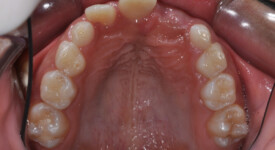

After Transformation!